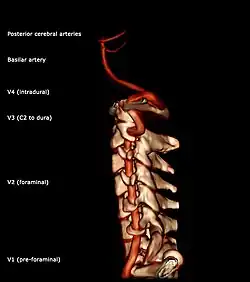

Segments of vertebral artery anterior projection

The vertebral artery may be divided into four parts:

The second (foraminal) part runs upward through the transverse foramina of the C6 to C2 vertebrae, and is surrounded by branches from the inferior cervical sympathetic ganglion and by a plexus of veins which unite to form the vertebral vein at the lower part of the neck. It is situated in front of the trunks of the cervical nerves, and pursues an almost vertical course as far as the transverse process of the axis.

The third (extradural or atlantic) part issues from the C2 foramen transversarium on the medial side of the Rectus capitis lateralis. It is further subdivided into the vertical part V3v passing vertically upwards, crossing the C2 root and entering the foramen transversarium of C1, and the horizontal part V3h, curving medially and posteriorly behind the superior articular process of the atlas, the anterior ramus of the first cervical nerve being on its medial side; it then lies in the groove on the upper surface of the posterior arch of the atlas, and enters the vertebral canal by passing beneath the posterior atlantoöccipital membrane. This part of the artery is covered by the Semispinalis capitis and is contained in the suboccipital triangle—a triangular space bounded by the Rectus capitis posterior major, the Obliquus superior, and the Obliquus inferior. The first cervical or suboccipital nerve lies between the artery and the posterior arch of the atlas.

Segments of vertebral artery lateral projectionThe fourth (intradural or intracranial) part pierces the dura mater and inclines medially to the front of the medulla oblongata; it is placed between the hypoglossal nerve and the anterior root of the first cervical nerve and beneath the first digitation of the ligamentum denticulatum. At the lower border of the pons, it unites with the vessel of the opposite side to form the basilar artery.